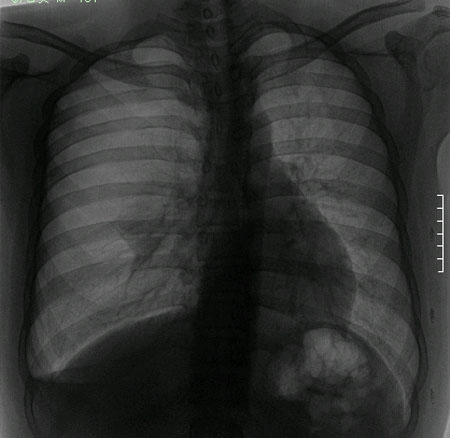

病人男,41岁。2001年2月体检时发现左胸腔大量积气,遂入院。查体:气管右移,左侧呼吸动度减弱、左肺叩诊鼓音、听诊呼吸音消失,心浊音界向右移位,心率86次/min.,律齐。x线胸片及ct扫描示左肺纹理消失,肺压缩100%,心脏、纵隔右移(图!、2)。诊断为左胸巨大型肺大皰。全麻下行开胸探查,术中见一巨大气囊占据整个胸腔,壁厚,韧度好,张力不大。基底位于叶间裂左肺下叶背段肺表面,肺实质正常无气肿表现。完整摘除气囊后移出,见其大小约40cm*20cm*13cm(图3),内无液体。术后10d病人痊愈出院。病理结果:囊壁为纤维结缔组织,部分区域胶原组织增生伴有变性,囊壁腔无内衬上皮(图4)。

图1 本例病人]线胸片示左肺空气囊肿 图2 ct显示左肺空气囊肿

本例病史无胸闷、气短等症状;影像学示气囊壁厚,病变区透亮度介于气胸与肺大皰之间,内无发丝样阴影,不伴有周围肺气肿;囊肿位于肺表面。壁厚,张力不高,在游离、切除过程中并不破裂,可与肺大皰相区别。另外,病人有长期吸烟史,每日30余支,术中却见肺表面如同正常小儿肺,无炭末、粉尘沉积,因此,该病可能为自幼存在的先天性疾病。